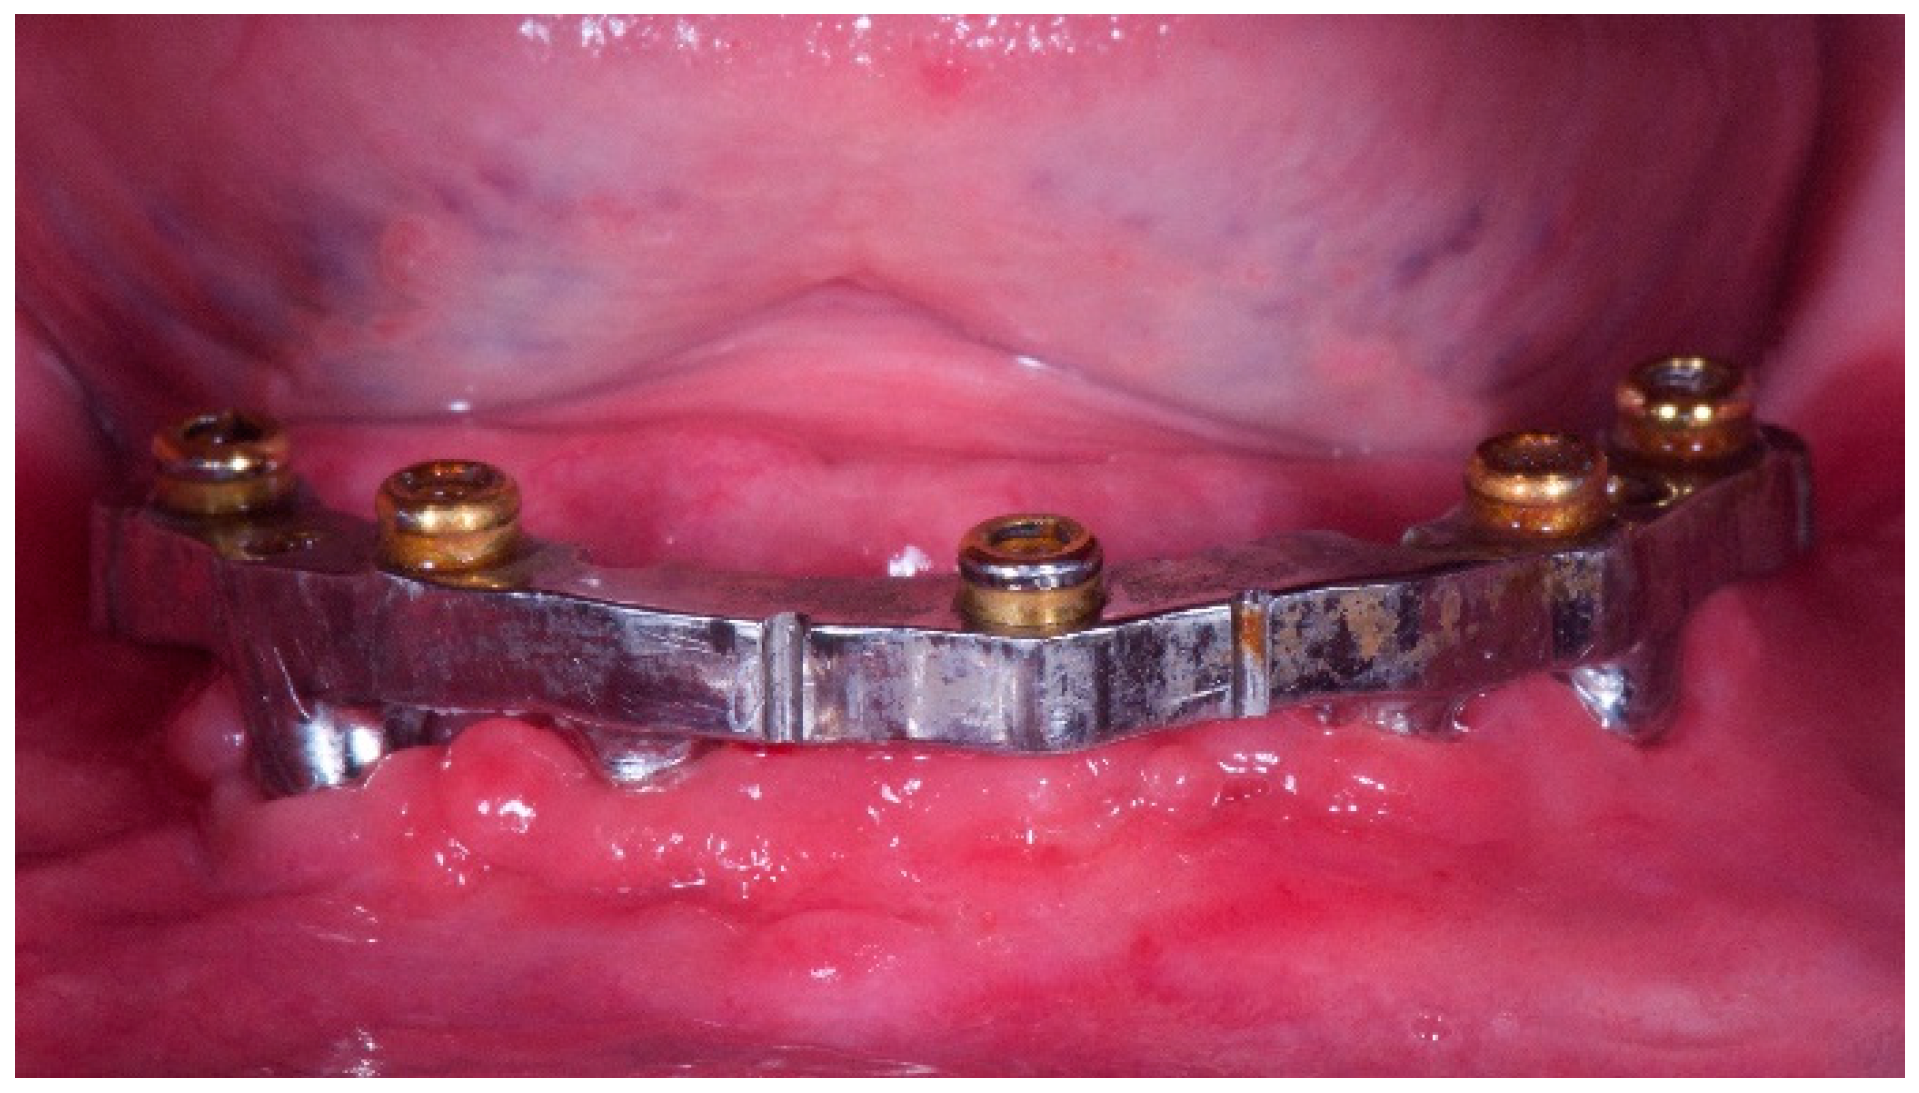

Patients were rehabilitated with both implant-retained or -supported overdentures. In case of implant-retained overdentures, pre-existing or a new developed complete removable dentures were used followed standardized techniques [25]. Implant-retained overdentures were delivered on 1 to 5 unsplinted implants. The following attachment systems were used: Equator attachments (OT Equator, Rhein83, Bologna, Italy), ball attachments (OT Cap, Rhein83), or Locator attachments (Zest Dental Solutions, Carlsbad, CA, USA) (Figure 1, Figure 2, Figure 3 and Figure 4). The Rhein83 OT Equator is a low profile castable and direct implant overdenture attachments with a low vertical profile of 2.1 mm and diameter of 4.4 mm. This system offers multiple solutions for overdenture treatment planning when vertical space limitations are a consideration.

Figure 3. Five-year follow-up of CAD/CAM mandibular overdenture with Locator attachments. Worn attachments in the retentive area, signs of wear due to the rigidity of the attack that makes it work are in the area of maximum circumference.

The elastic material of the retentive matrix of OT Equator may allow to distribute on a larger surface the retentive capacity, resulting in a longer lasting retention due to the wear reduction at the circumference.

The rigid attachments such as the Locators only work on the circumference and have very thin rigid material matrices.

It should be noticed that the retentive force of the Locator and OT Equator attachments is obtained through mechanical interlocking and frictional contact between the male and female. An ideal attachment system should provide a high and stable retentive force with a low lateral force to the implant, not only in the parallel placement of the implant, but also in the implant inclination during recurrent dislodging [51]. The retention feature of the Locator and OT Equator attachments is a frictional contact, which derives from a dimensional misfit between the slightly oversized male and the smaller diameter of the female abutment.

Both attachments investigated in this paper had the same clinical advantages, nevertheless, a less number of complications and prosthetic failure can be expected using OT Equator. A possible explanation could be that the retentive caps of the OT equator are made of elastic material while Locator uses rigid material. Elastic material seems to work better than rigid. Furthermore, the smaller size of the OT Equator may allow for an improved design of the overdenture leaving more space for the veneering materials. Furthermore, by exploiting the low profile of the OT Equator the clinician can better manage the prosthetic spaces according to a better aesthetic result.